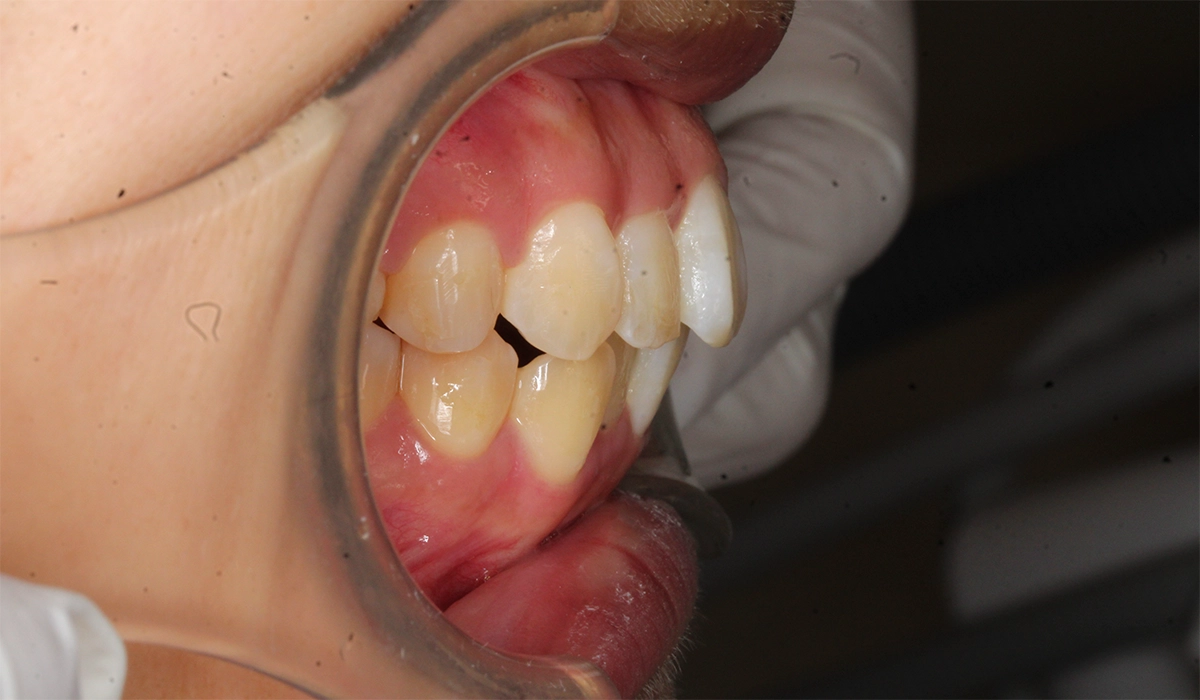

術前:右側